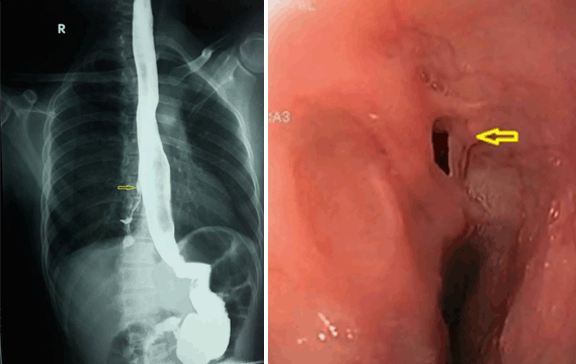

Barium esophagogram showing esophagobronchial fistula between the middle third of the esophagus and the right lower bronchus with downward passage of barium (shown with arrow). Endoscopic findings: The fistula opening in the middle esophagus (arrow). (Page 71–72)